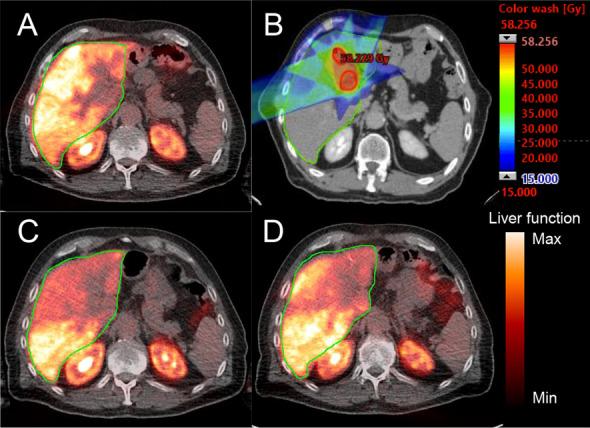

Stereotactic body radiotherapy (SBRT) is increasingly used for treatment of liver tumors but the effect on metabolic liver function in surrounding tissue is largely unknown. Using 2-deoxy-2-[F]fluoro-D-galactose ([F]FDGal) positron emission tomography (PET)/computed tomography (CT), we aimed to determine a dose-response relationship between radiation dose and metabolic liver function as well as recovery.

One male subject with intrahepatic cholangiocarcinoma and five subjects (1 female, 4 male) with liver metastases from colorectal cancer (mCRC) underwent [F]FDGal PET/CT before SBRT and after 1 and 3 months. The dose response was calculated using the data after 1 month and the relative recovery was evaluated after 3 months. All patients had normal liver function at time of inclusion.

A linear dose-response relationship for the individual liver voxel dose was seen until approximately 30 Gy. By fitting a polynomial curve to data, a mean TD of 18 Gy was determined with a 95% CI from 12 to 26 Gy. After 3 months, a substantial recovery was observed except in tissue receiving more than 25 Gy.

[F]FDGal PET/CT makes it possible to determine a dose-response relationship between radiation dose and metabolic liver function, here with a TD of 18 Gy (95% CI 12-26 Gy). Moreover, the method makes it possible to estimate metabolic recovery in liver tissue.

立体定向体放射治疗(SBRT)越来越多地用于治疗肝脏肿瘤,但周围组织代谢肝功能的影响在很大程度上尚不清楚。本研究采用 2-脱氧-2-[F]氟-D-半乳糖([F]FDGal)正电子发射断层扫描(PET)/计算机断层扫描(CT),旨在确定辐射剂量与代谢肝功能以及恢复之间的剂量反应关系。

1 名男性肝内胆管细胞癌患者和 5 名(1 名女性,4 名男性)结直肠癌(mCRC)肝转移患者在 SBRT 前、治疗后 1 个月和 3 个月进行[F]FDGal PET/CT 检查。使用 1 个月后的数据计算剂量反应,并用 3 个月后的相对恢复来评估。所有患者在纳入时肝功能正常。

个体肝像素剂量的线性剂量反应关系可见至约 30Gy。通过对数据拟合多项式曲线,得出平均 TD 为 18Gy,95%CI 为 12-26Gy。3 个月后,除了接受超过 25Gy 剂量的组织外,观察到明显的恢复。

[F]FDGal PET/CT 可用于确定辐射剂量与代谢肝功能之间的剂量反应关系,此处的 TD 为 18Gy(95%CI 12-26Gy)。此外,该方法可用于估计肝脏组织的代谢恢复。